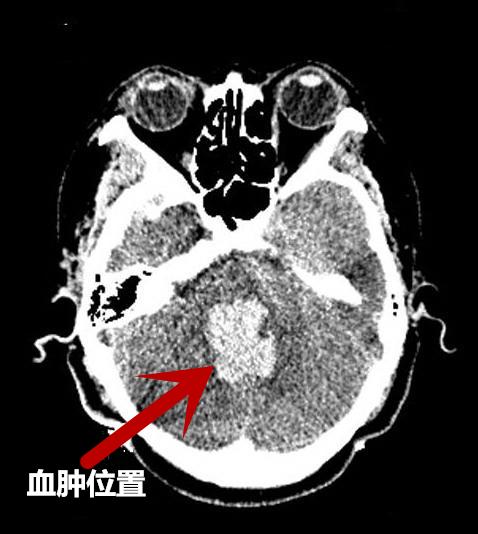

“入院时,患者意识呈深昏迷状态,血压210/116mmHg,自主呼吸急促,面色紫绀,立即行气管插管,呼吸机辅助呼吸,头颅CT提示:脑干出血破入脑室,出血量约13ml,因患者病情危急,转入神经外科ICU给予积极治疗维持生命体征。”接诊的急诊科医生回忆说。

术后复查CT,与术前CT对比血肿明显减少

术后15天复查CT

与术前CT对比血肿已基本清除